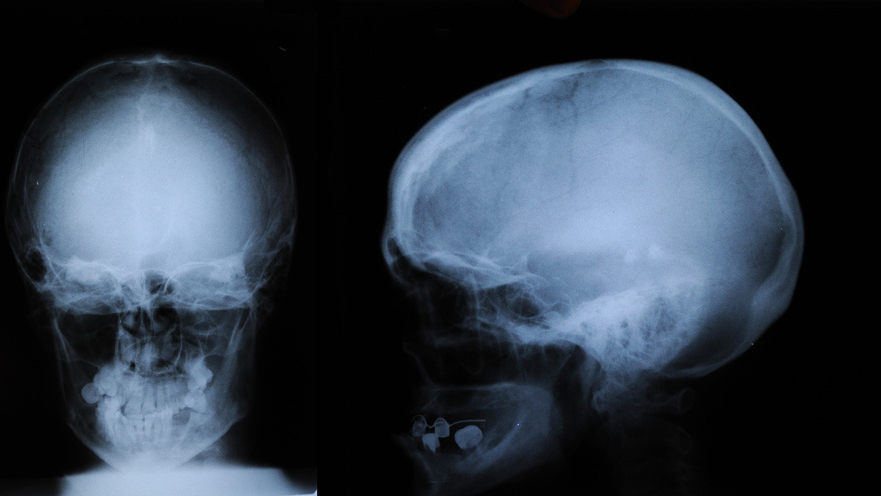

Рентгенография черепа и позвоночника: изображение и диагностика